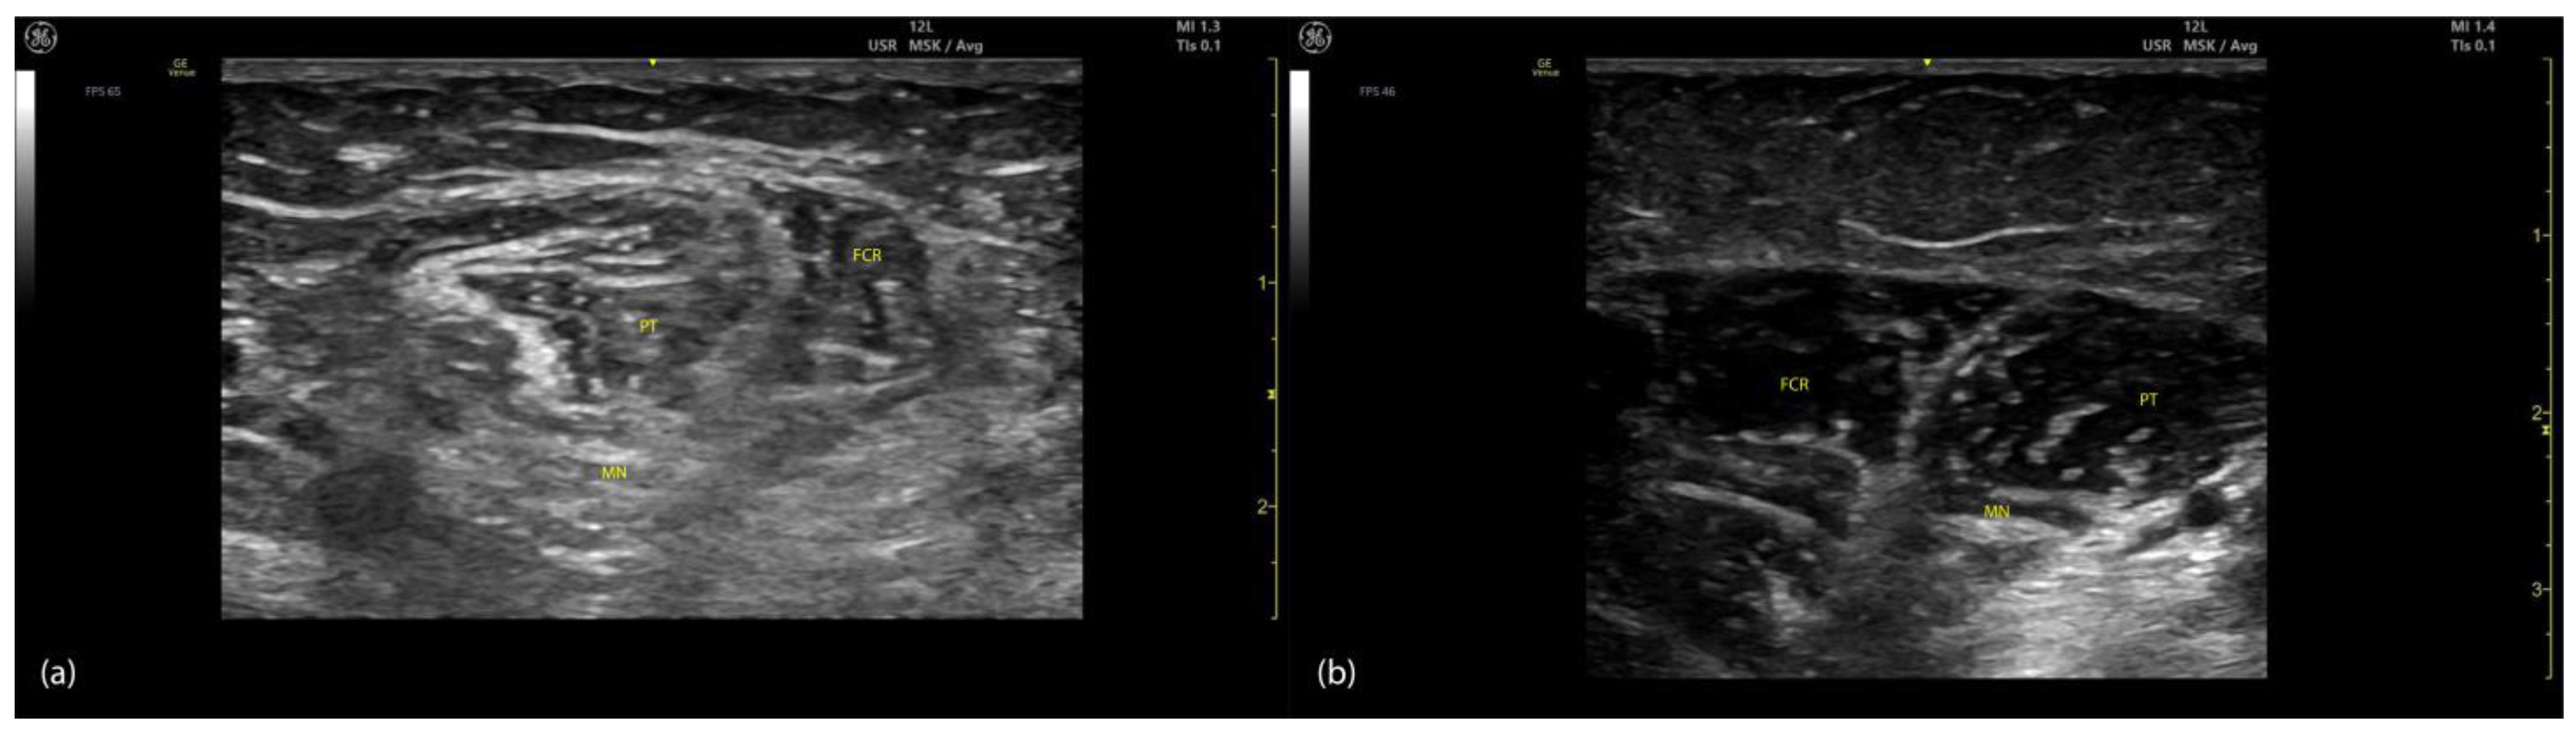

2.1.2. Ultrasound Identification

- The PT, which appears oval-shaped on the lateral side;

- The flexor carpi radialis (FCR), which appears triangular-shaped on the medial side [8].

2.1.3. Key Ultrasound Landmarks (Figure 1)

- Muscle position: The PT is the first muscle mass from radial to ulnar on the volar aspect of the forearm [9].

- Intramuscular tendon: In the lateral portion of the muscle, it is positioned longitudinally along the muscle at this level.

- Internal fascia: The fascia separates the humeral (PTHH) and ulnar heads (PTUH) of the PT, while the external fascia distinctly demarcates the PT from adjacent muscle masses, facilitating precise BoNT-A injection.

- Median nerve: The nerve is located deep to the PT, approximately 2 cm distal to the elbow crease. Dynamic evaluation cranially towards the arm reveals the nerve transitioning to the lateral aspect of the muscle alongside the brachial artery [10].

- Dynamic evaluation (Video S1): Scanning proximally toward the medial epicondyle shows an increase in the PT muscle belly size and a concurrent decrease in the size of the FCR. At this level, the intramuscular fascia specific to the PT becomes evident, separating the two muscle heads—the humeral head and the ulnar head—allowing for individual targeting [11].